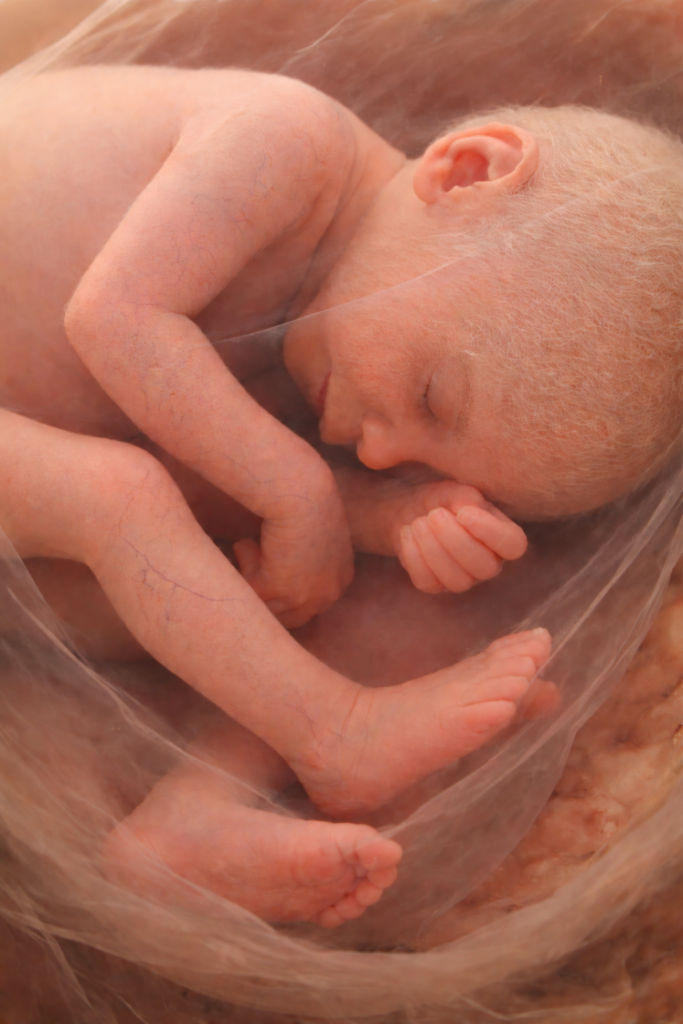

Week 17

Rond deze termijn vormt zich een vetlaagje rond de huid (vernix). Dit laagje huidsmeer beschermt je baby tegen het inwekende effect van het vruchtwater en tegen infecties. In week 17 is het gehoor zover ontwikkeld dat het kindje geluiden buiten de baarmoeder kan horen. Hij of zij zal wennen aan jullie stemmen en deze dan ook zeker herkennen na de geboorte. Begin dus maar alvast met voorlezen en met het laten luisteren naar je favoriete muziek! Ook de tastzin is ontwikkeld: het kindje kan aanrakingen van buitenaf voelen en kan ook zijn eigen bewegingen voelen.

15 cm

160 g